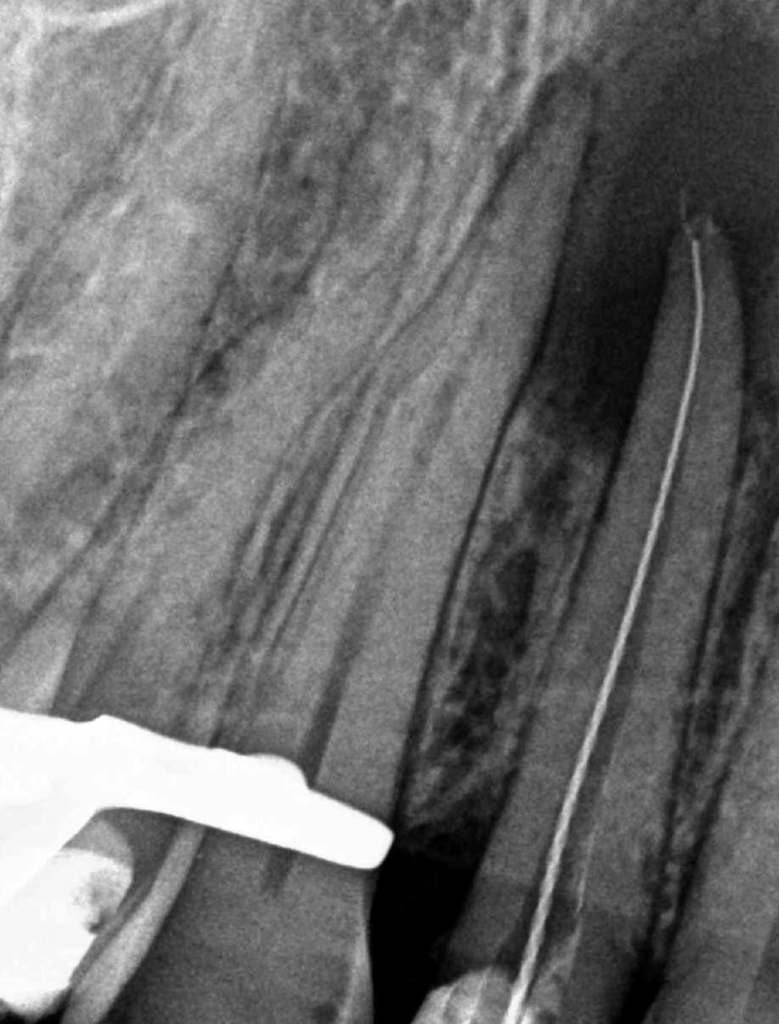

CALCIFICADOS

Premolar calcificado lesion